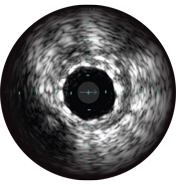

Intravascular ultrasound (IVUS) is a catheter-based imaging technology that allows physicians to visualize blood vessels from the inside out. Cross-sectional images help assess presence and extent of disease, plaque geometry and morphology, guide wire position during lesion crossing, and stent position post-treatment. The imaging transducer emits high-frequency sound waves that echo off vessel walls and are sent back to the system in varying intensities depending on the tissue. System electronics process the signal to display the cross-sectional image.

Stent expansion is a predictor of stent thrombosis and restenosis. Target minimum stent areas post-PCI may include: ≥80% of the average reference lumen areas, 6 mm2 for DES in non-LM vessels, or other criteria depending on the type of PCI. IVUS helps document your result.2